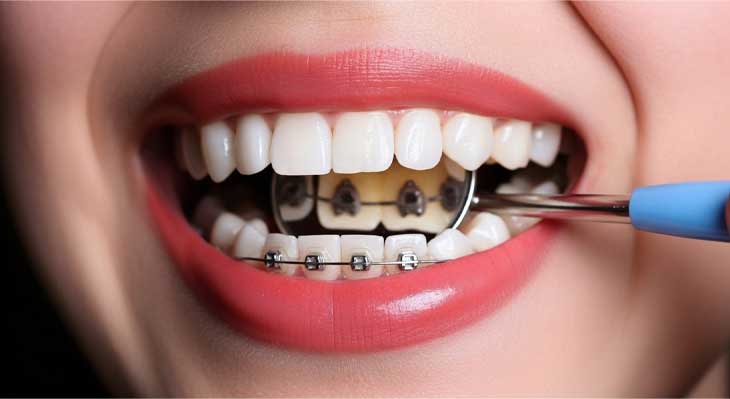

ارتودنسی لینگوال که به آن ارتودنسی پشت دندانی یا مخفی نیز گفته می شود، پیشرفته ترین و پنهان ترین روش در میان سیستم های ارتودنسی ثابت است. در این تکنیک منحصر به فرد، تمام اجزای دستگاه ارتودنسی، شامل براکت ها و سیم ها، به جای سطح بیرونی، بر روی سطح داخلی (زبانی) دندان ها نصب می شوند. این ویژگی باعث می شود که دستگاه از بیرون کاملا غیر قابل مشاهده باشد و بیمار بتواند بدون هیچگونه نگرانی از بابت ظاهر خود، دوره درمان را سپری کند. این روش یک گزینه ایده آل برای بزرگسالان، افراد مشهور و تمام کسانی است که به دنبال دستیابی به یک لبخند زیبا بدون دیده شدن بریس های ارتودنسی هستند.

ارتودنسی لینگوال یک روش درمانی کاملا تخصصی است. در این روش از دستگاه های ثابت برای مرتب کردن دندان ها استفاده می شود. تفاوت اصلی و انقلابی این روش در محل قرارگیری دستگاه است. تمام اجزای بریس ارتودنسی به سطح پشتی دندان ها، یعنی سمتی که با زبان در تماس است، چسبانده می شوند. این موقعیت استراتژیک باعث می شود که درمان از دید دیگران کاملا پنهان بماند. هیچکس متوجه نخواهد شد که شما تحت درمان ارتودنسی قرار دارید. این ویژگی، بزرگترین مزیت این سیستم درمانی محسوب می شود.

عملکرد این روش کاملا مشابه بریس های سنتی است. براکت های سفارشی به دندان ها متصل می شوند. سیم ارتودنسی از میان این براکت ها عبور می کند. این سیم با اعمال نیروهای ملایم و مداوم، دندان ها را به تدریج به سمت موقعیت ایده آل خود حرکت می دهد. متخصص ارتودنسی در هر جلسه ویزیت، این سیم ها را تنظیم می کند. این تنظیمات برای ادامه روند حرکت دندان ها ضروری است. این سیستم قادر است پیچیده ترین مشکلات دندانی را نیز با دقت بالایی درمان کند.

به دلیل پیچیدگی های فنی و نیاز به دسترسی دشوارتر، این درمان نیازمند مهارت و تخصص بسیار بالای ارتودنتیست است. براکت های مورد استفاده در این روش نیز معمولا با استفاده از تکنولوژی های دیجیتال و به صورت کاملا سفارشی برای هر دندان بیمار ساخته می شوند. این سفارشی سازی، دقت و کارایی درمان را به حداکثر می رساند. این روش ترکیبی از کارایی بالای بریس ثابت و زیبایی مطلق است.